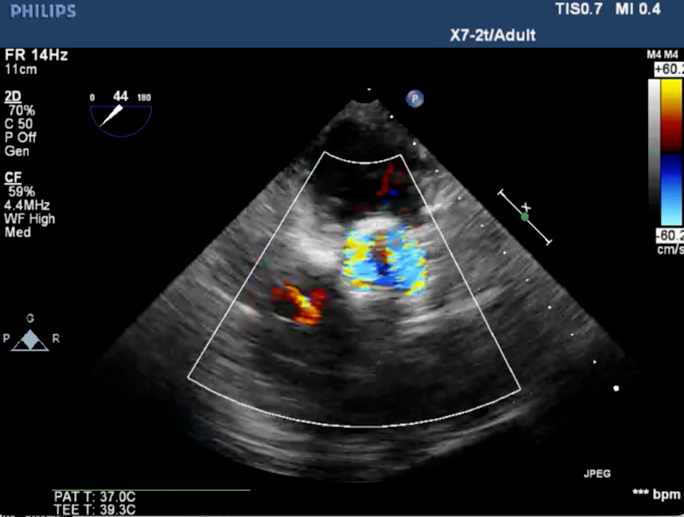

心脏超声诊断:主动脉瓣明显增厚钙化伴极重度狭窄及轻度反流(最大流速: 6.07 m/s,峰值压差:147 mmHg,平均压差:65 mmHg),左室壁明显增厚致乳头肌水平以上至心尖部梗阻(峰值压差123 mmHg),轻度二尖瓣狭窄;

4、术后心电监护未见传导阻滞,心超提示人工主动脉瓣工作良好,瓣叶启闭正常,主动脉瓣峰值流速2 m/s,平均跨瓣压差6 mmHg,轻度瓣周漏。